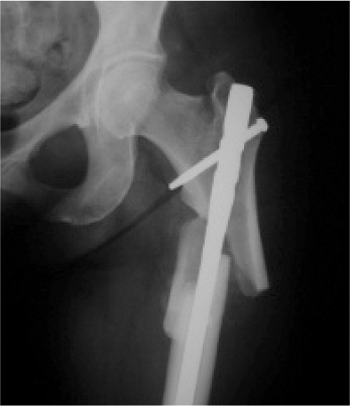

malfunction while jumping. On impact, he had a closed, displaced,

proximal, femur fracture (Fig. 20.46). The

patient underwent reamed, static, reconstruction nailing. His fracture

united at 3 months, and he returned to his work without restrictions.

This fracture pattern probably represents the ideal indication for a

reconstruction nail; that is, it was a subtrochanteric fracture with

loss of medial cortical stability and with fracture of the lesser

trochanter (Russell–Taylor IB). The fracture did not extend into the

piriformis fossa.

![]() |

Figure 20.46. A,B. Subtrochanteric fracture caused from parachuting accident. Stabilization with Russell-Taylor reconstruction nail, static mode.